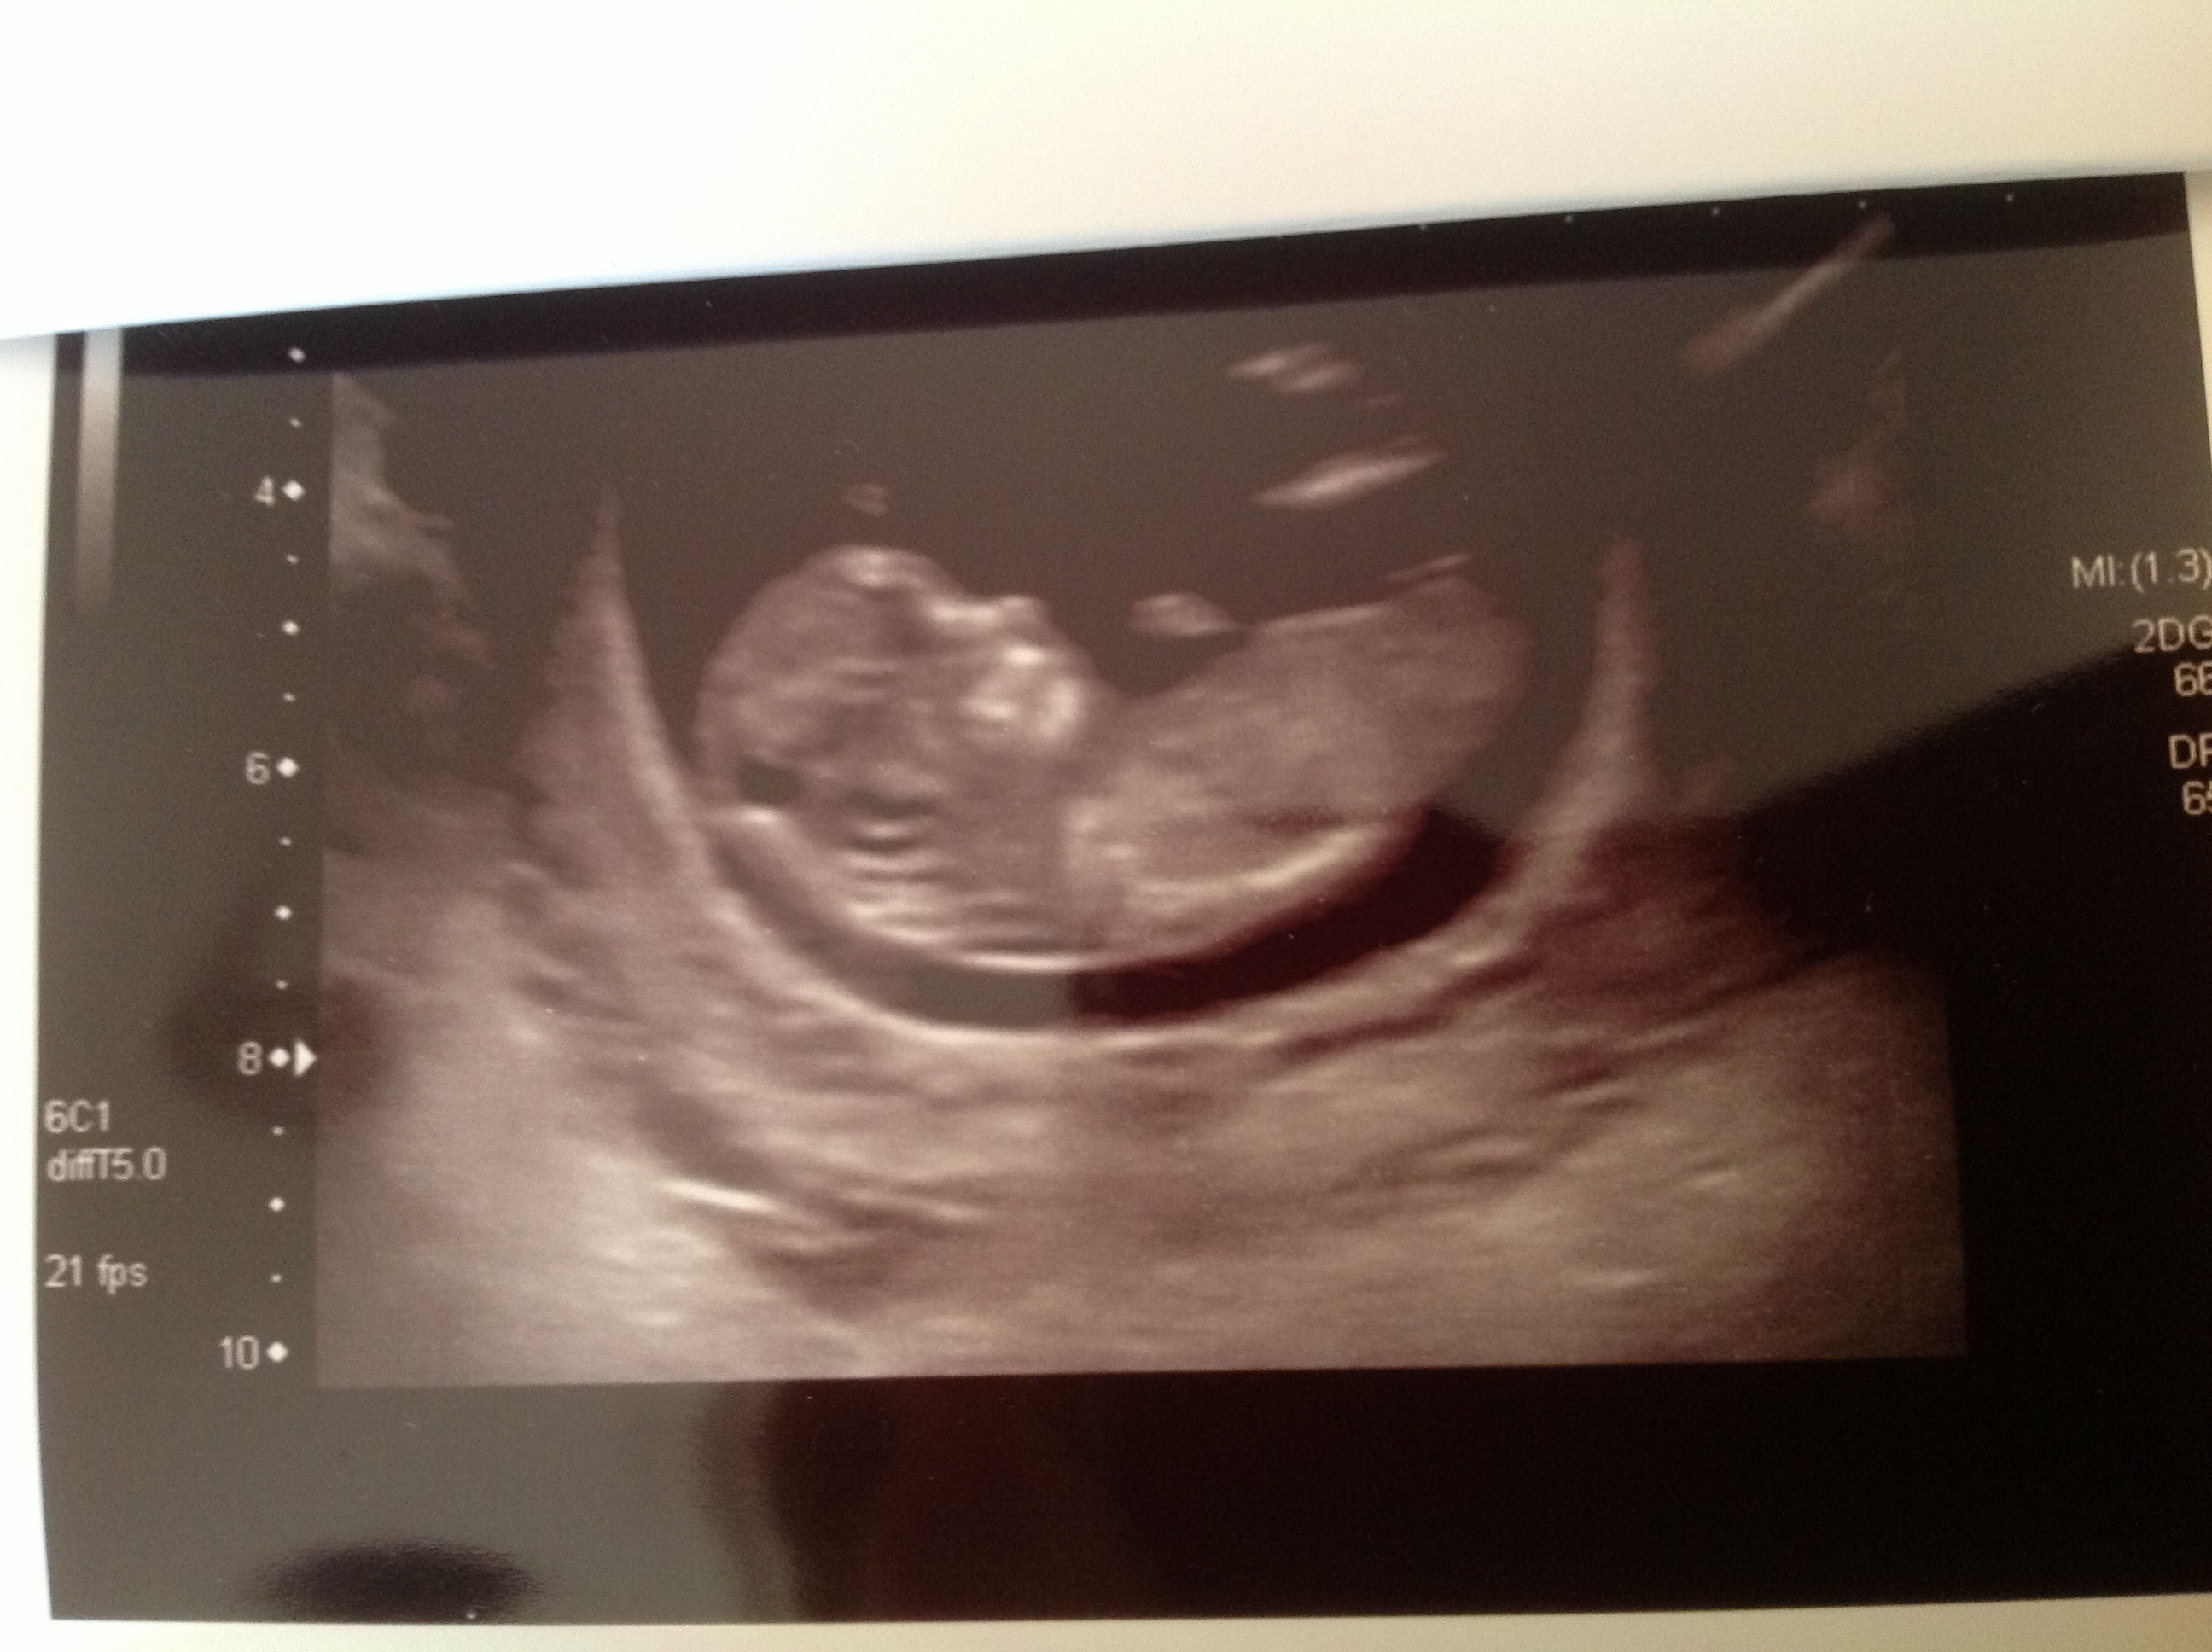

I've had a couple of scans. The first 2 pictures are at 12 weeks, 2 days. Not sure if they caught the nub?

Attachment 12283